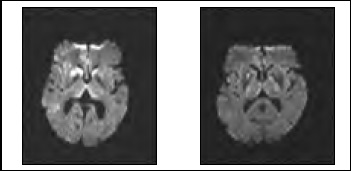

Debido a que la paciente provenía de provincia, se decidió hospitalizarla para su estudio. Se realizó una resonancia magnética cerebral que mostró en secuencia de difusión signos involutivos, hiperintesidades en núcleo caudado y lenticular derecho, talámico medial bilateral y cortical frontal derecho (Figura 1). Todos los hallazgos con discreta representación en FLAIR y mapa ADC. El EEG en vigilia y somnolencia dentro de límites fisiológicos. Hemograma, perfil bioquímico y perfil tiroídeo normales. VDRL no reactivo. Nivel plasmático de vitamina B12 en rango normal. Punción lumbar: LCR claro, estudio citoquímico normal, Gram sin bacterias, tinta china negativa, VDRL no reactivo. Proteína 14-3-3 negativa.

Figura 1. RM cerebral, en secuencia de difusión, de los casos N°1 y N°3 respectivamente, que muestran hiperintensidades anormales en lenticulares y tálamos.

Se realizó un EEG que mostró una lentitud difusa de los ritmos de base con actividad epileptiforme lateralizada y periódica (PLEDS) enregión fronto-temporal derecha. TAC cerebral contrastada normal. Se realizó una resonancia magnética cerebral (Figura 1) que mostró en secuencia de difusión hiperseñales en la cabeza y cuerpo de ambos núcleos caudados, la mitad anterior del núcleo lenticular derecho e hiperseñal “en palo de jockey” en ambos tálamos. Múltiples focos de hiperintensidad en la corteza cerebral de predominio en región parietal derecha y fronto parietal mesial derecha. Los hallazgos descritos eran altamente compatibles con ECJ. LCR con citoquímico normal. Proteína 14-3-3 negativa. Se diagnóstico una ECJ esporádica, la paciente siguió con un deterioro cognitivo progresivo y falleció posteriormente en su domicilio.

Todos nuestros pacientes tenían alteraciones en la resonancia magnética cerebral típicas de la ECJ. En 2 de ellos las hiperintensidades de los lenticulares y tálamos eran predominantes por sobre las de la corteza. No existen evidencias publicadas acerca de una relación entre las alteraciones de la resonancia magnética cerebral y el insomnio en pacientes con ECJ. Meissner, en un estudio de 212 casos confirmados describió que las hiperintensidades típicas de ECJ se asociaban precozmente a demencia, mayor frecuencia de depresión y trastornos sensoriales. No se menciona al insomnio(10). En el IFF la resonancia magnética habitualmente es normal; sin embargo, los estudios con PET-scan describen alteraciones en el metabolismo del tálamo.